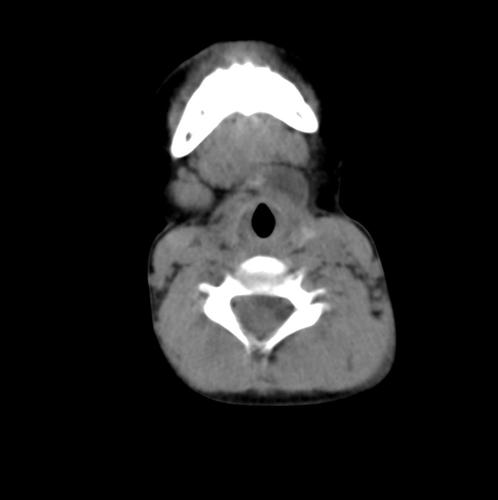

核心提示:甲状舌骨囊肿ct病例(影像图)